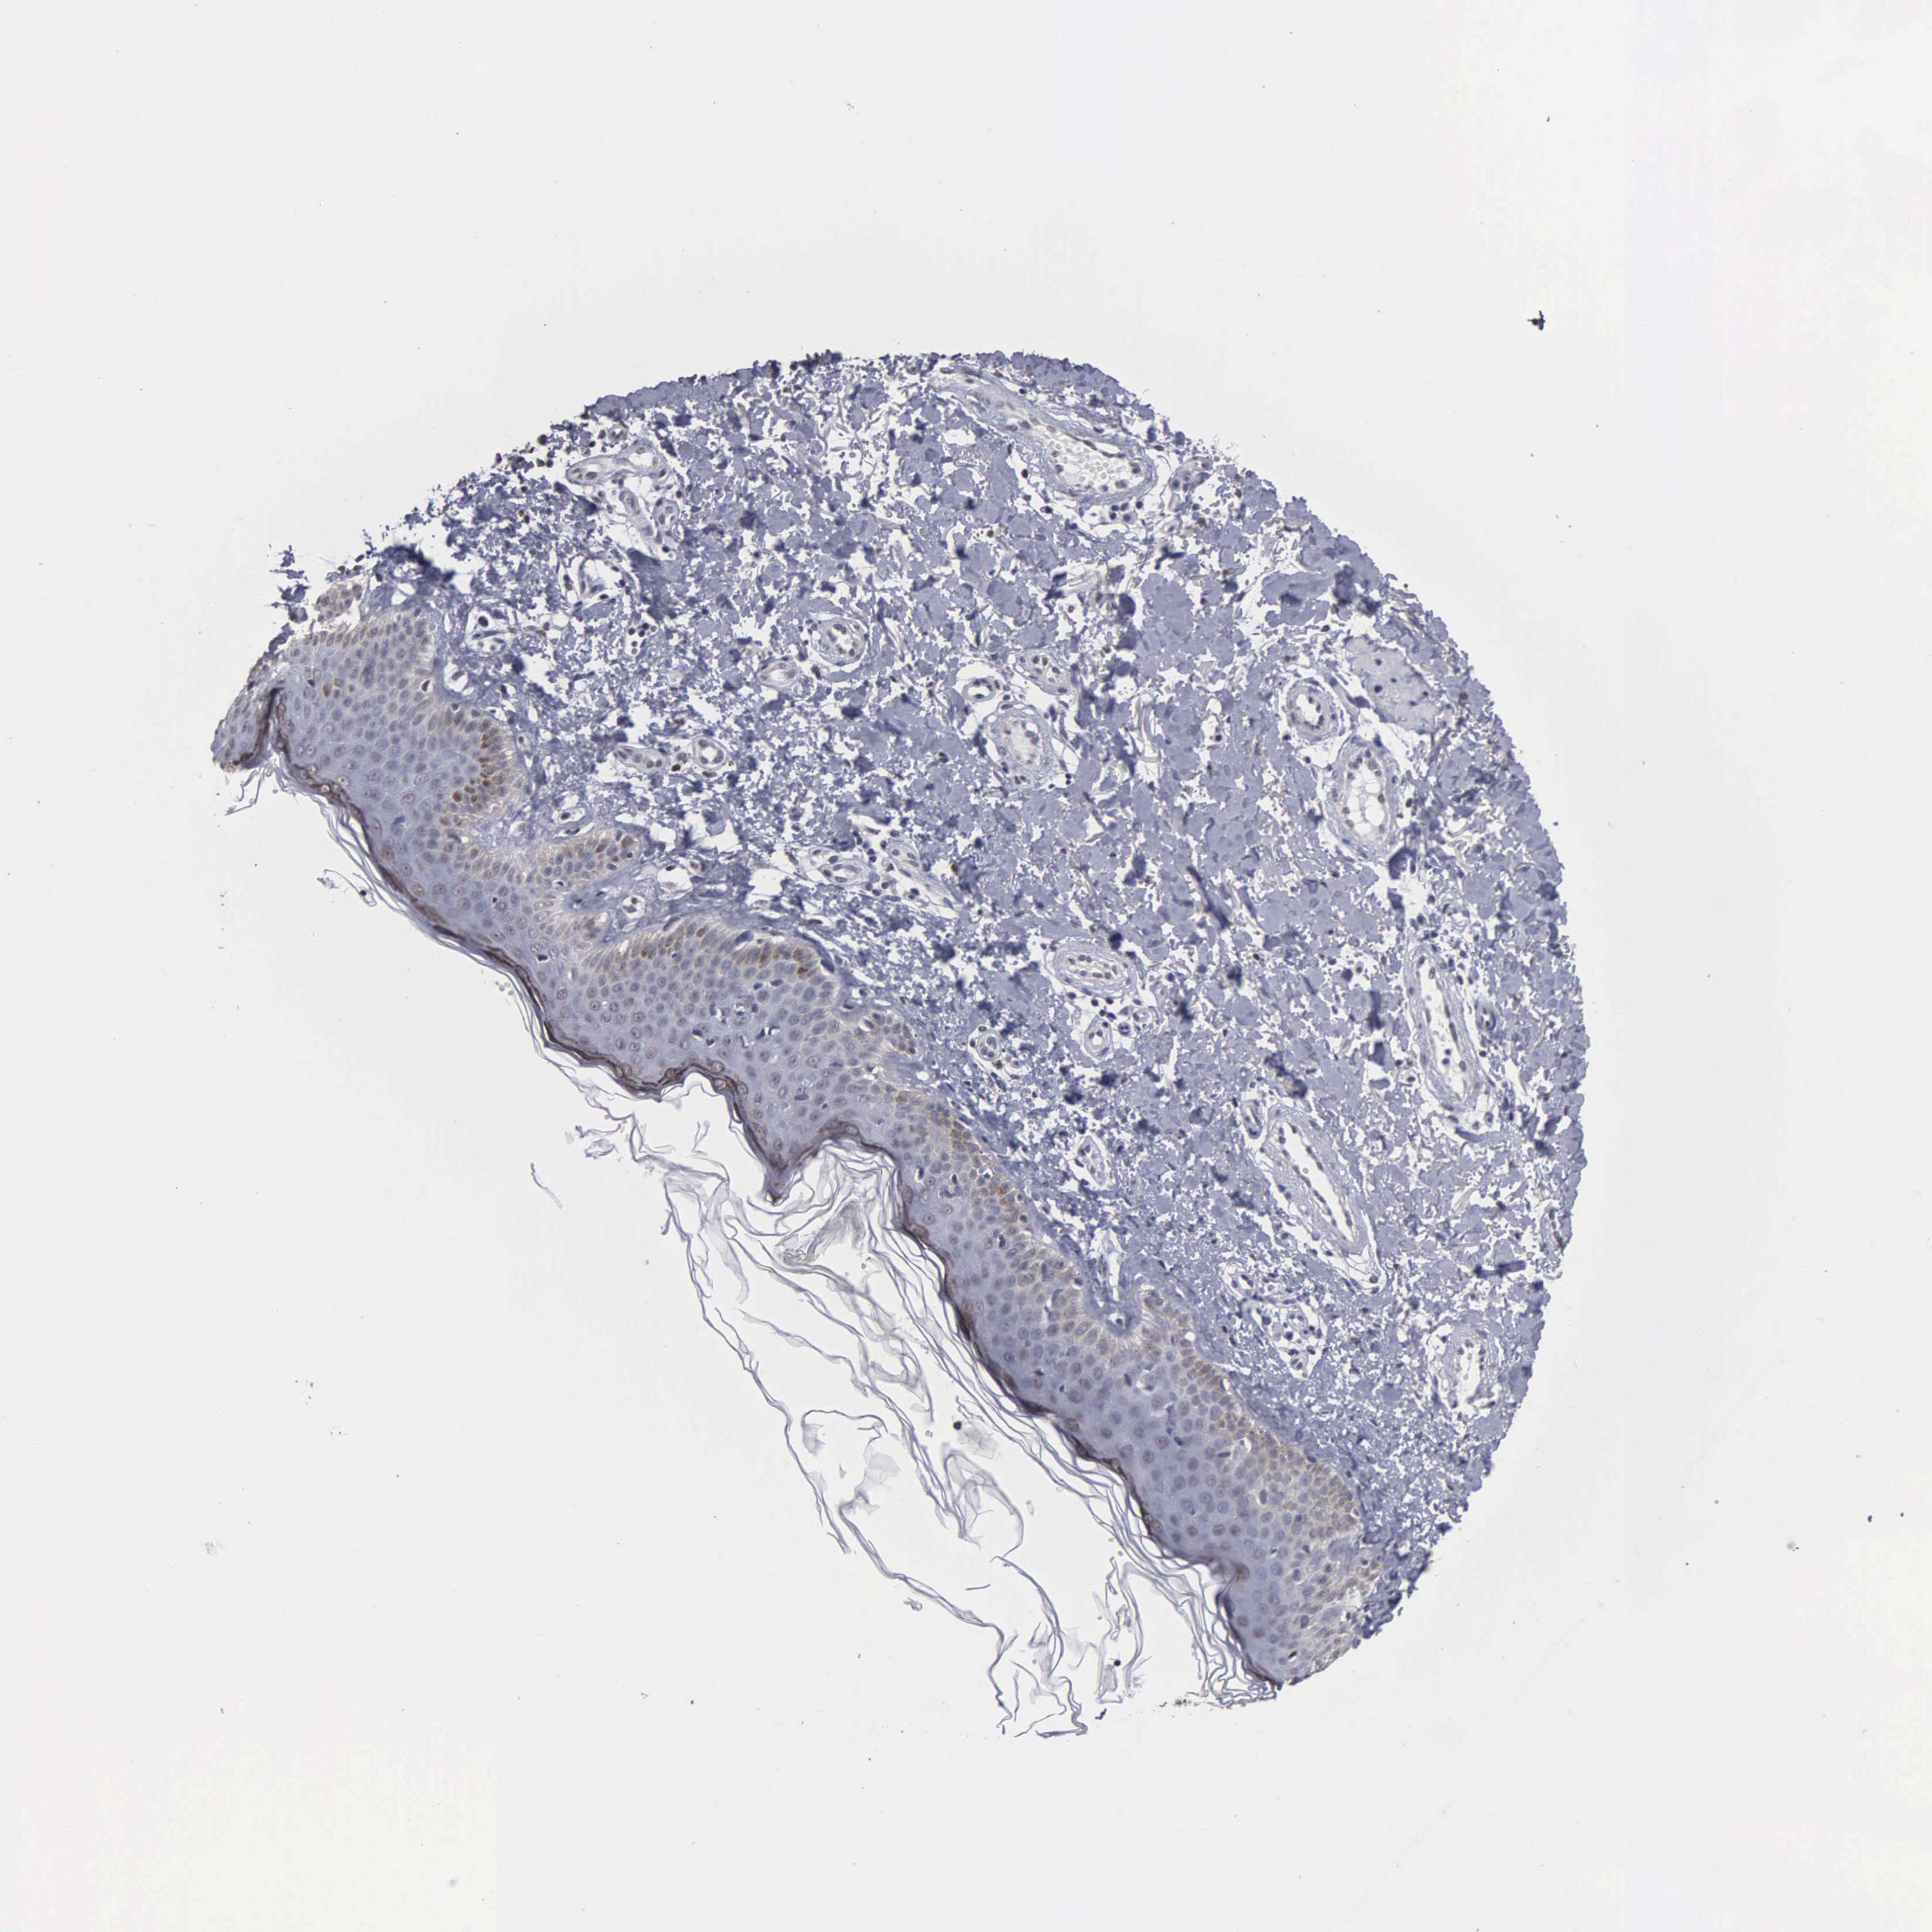

MELANOMA - Protein expressioni

A mouse-over function shows sample information and annotation data. Click on an image to view it in a full screen mode. Samples can be filtered based on level of antibody staining by selecting one or several of the following categories: high, medium, low and not detected. The assay and annotation is described here.

Note that samples used for immunohistochemistry by the Human Protein Atlas do not correspond to samples in the TCGA dataset.

Antibody stainingi

Antibody staining in the annotated cell types in the current human tissue is reported as not detected, low, medium, or high, based on conventional immunohistochemistry profiling in selected tissues. This score is based on the combination of the staining intensity and fraction of stained cells.

Each image is clickable and will lead to virtual microscopy that enables deeper exploration of all samples and also displays staining intensity scores, fraction scores and subcellular localization as well as patient and tissue information for each sample.

Antibody HPA000728

Antibody HPA076321

Malignant melanoma, NOS

Malignant melanoma, Metastatic site